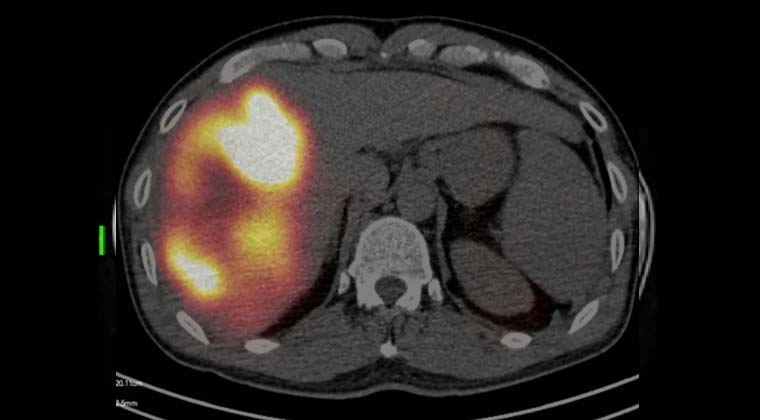

Перед лечением была выполнена имитационная оценка с использованием иттрий-90: в артерии, питающие опухоль, был введён MAA с последующим проведением SPECT-сканирования для подтверждения распределения кровотока и границ безопасности. После этого была проведена терапия смоляными микросферами иттрия-90, при которой рассчитанная доза микросфер по плану была введена в опухоль-питающие артерии с обеспечением адекватного покрытия очага.

Наблюдение и исход: Контрольные обследования показали выраженное уменьшение размеров опухоли и регресс опухолевого тромба воротной вены. По данным визуализации был отмечен некротический ответ очагов.

После MDT-оценки и подтверждения возможности хирургического вмешательства было выполнено оперативное удаление некротизированной опухоли. По данным патоморфологического исследования подтверждён некроз опухоли. Общее состояние пациента постепенно улучшилось, качество жизни повысилось.

(Достигнуто полное покрытие гигантской опухоли микросферами иттрий-90)